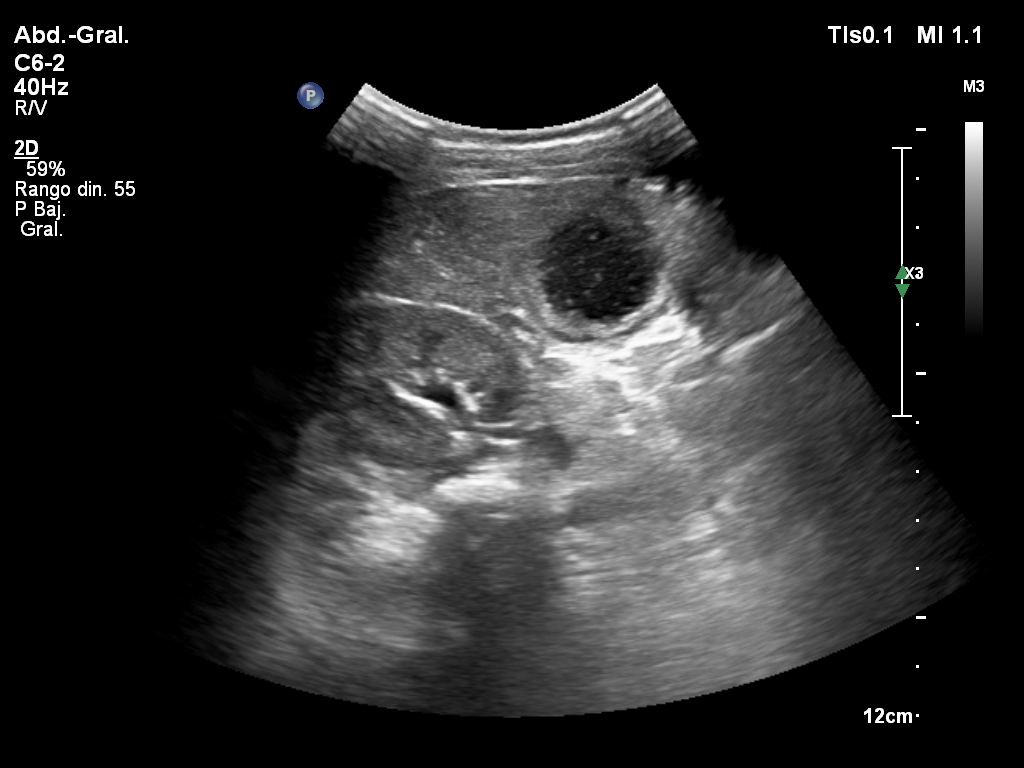

Dolor en hipocondrio derecho

Femenina de 31 años